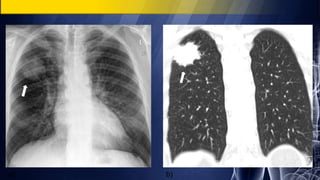

Asymptomatic 35-year-old man

• PA chest radiograph demonstrates a well-marginated polylobular mass in the

right lower lobe.

Coned-down contrast-enhanced chest CT (lung and mediastinal windows)

demonstrates a polylobular right lower lobe mass with well-defined borders and

intrinsic homogeneous fluid attenuation contents.

Pulmonary Cystic Hydatid Disease (Echinococcosis)

Asymptomatic 35-year-old man •PA chest radiograph demonstrates a well-marginated polylobular mass in the right lower lobe. Coned-down contrast-enhanced chest CT (lung and mediastinal windows) demonstrates a polylobular right lower lobe mass with well-defined borders and intrinsic homogeneous fluid attenuation contents. Pulmonary Cystic Hydatid Disease (Echinococcosis)